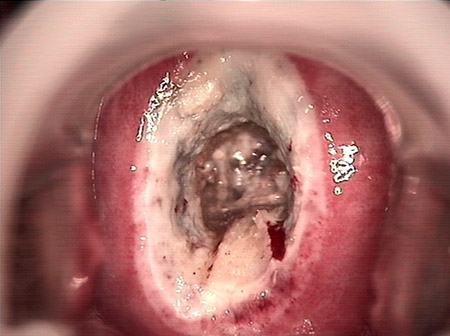

• CIN 2-3 修復(fù)后CIN 2-3 修復(fù)后

• CIN 2-3 修復(fù)后(圖2)CIN 2-3 修復(fù)后(圖2)